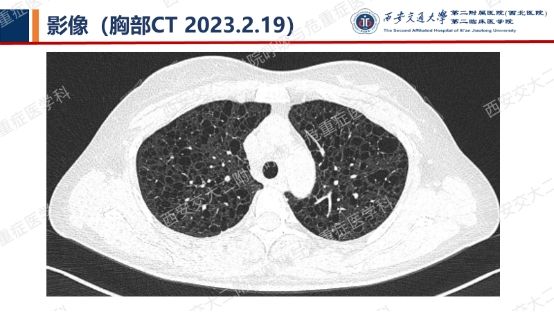

阅影探案,析病寻踪 // 第一期(上)

结合以上患者病史及胸部CT,第一诊断分别考虑???欲知答案,且看后期!!!